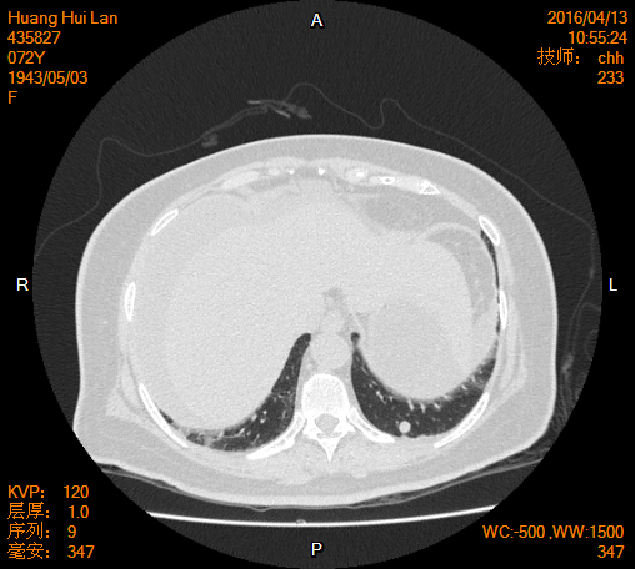

2016-04-13胸腹盆CT